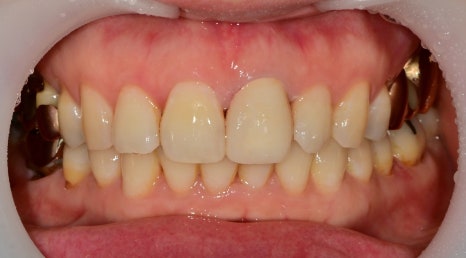

오래전에 대문니에 신경치료를 받으신 환자분이십니다.

치아 주변 플라그도 쌓여있어 잇몸치료도 필요해 보이십니다.

치료 후 시간이 지남에 따라 내부 재료의 변색과

신경치료를 위해 입구를 만든 부분에

충전해 놓은 재료의 오염에 의해 치아가 검게 보입니다.

엑스레이 상에서 뿌리 쪽 염증은 확인되지 않아

내부 오염된 부위를 깨끗이 제거한 후 새로운 충전재를 충천하고

보철 제작을 하기로 했습니다.

전후 사진 비교

이렇게 앞니의 보철치료는

기능적 뿐만 아니라 심미적인 요인도

작용하기 때문에 치료 결정에는

여러 요인이 작용하는 부분입니다.